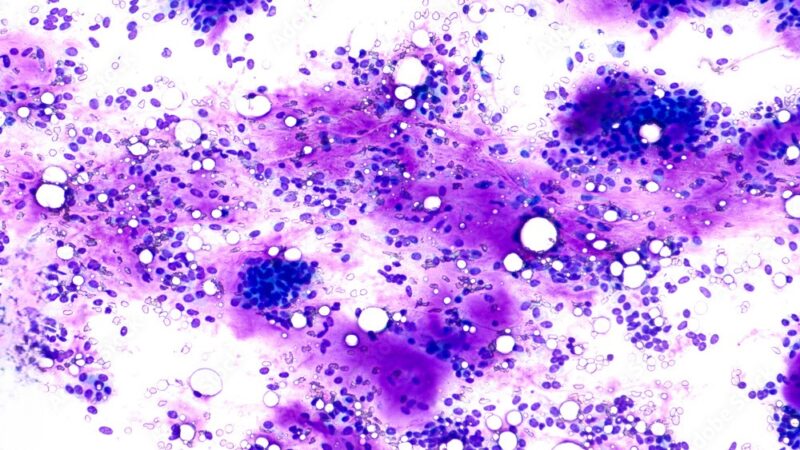

Fine Needle Aspiration Cytology (FNAC) is a minimally invasive diagnostic procedure used to assess lumps or masses in various parts of the body. It involves using a thin, hollow needle to extract cells from the suspicious area, which are then examined under a microscope.